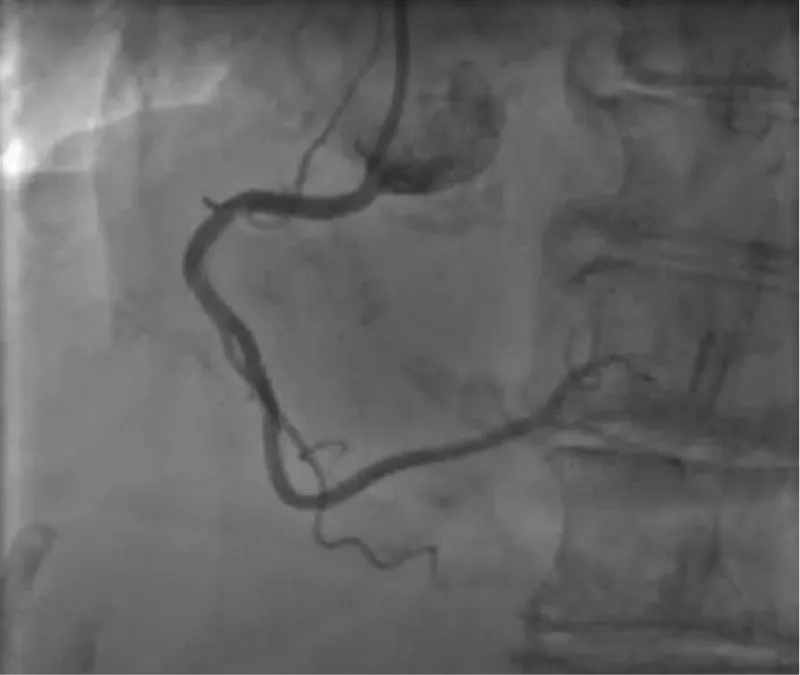

The clinical case concerns an 81-year-old woman with a history of systemic arterial hypertension, hypercholesterolemia, paroxysmal atrial fibrillation, chronic kidney disease, iron-deficiency anemia, and bilateral carotid atheromatosis for which she underwent a Carotid Endarterectomy (CEA) procedure. Additionally, she had a history of breast carcinoma, treated with surgery, subsequent chemotherapy, and ongoing Letrozole therapy. In 2019, the patient presented to the emergency department due to exertional dyspnea and low-threshold angina. During hospitalization, high average ventricular response (109 BPM) atrial fibrillation was diagnosed. Routine lab tests showed rising of hsTN-I (peak 800 pg/dL) and pro-BNP (peak 2476 pg/mL) and anemia Hb 9.1 g/dL. Echocardiography revealed severe depression of the left ventricular function (ejection fraction of 30%, with antero-apical akinesia) and low-flow-low-gradient aortic stenosis (mean gradient of 26 mmHg and AVAi of 0.5 cmq/m2 and SVi 29 mL/m2). So it was performed a Dobutamine stress Echo showed a rise of SVi up to 38 mL/m2 and a mean aortic gradient of up to 48 mmHg. Coronary angiography showed the right dominant coronary artery, of good caliber and course, with no angiographically significant lesions (Figure 1). The Left Main artery, with good caliber, had a 90% calcific stenosis at the distal segment, involving the proximal segment of the Left Anterior Descending artery. The Left Circumflex artery, with good caliber and course, presented a 30% ostial stenosis. The Intermediate Branch, with good caliber and course, showed 80% stenosis at the proximal segment (Figure 2). The Left Anterior Descending artery, also of good caliber and course, was diffusely atherosclerotic with a long, severely calcific 80% stenosis at the mid-distal segment (Figure 3). Therefore, the case was discussed by a multidisciplinary Heart team at our center. The STS score calculated indicated a mortality risk of 11.4%. Due to this high risk, surgical treatment was not considered, and the patient underwent a four-step percutaneous intervention. Before the intervention, a CT angiography was performed, revealing an aortic annulus area of 433.2 mm2, a perimeter of 75.3 mm, and a coronary height from the annulus of 10 mm. The right common femoral artery mean diameter was 6.1 mm2 and the external iliac artery was 8.4 mm2 with moderate tortuosity without significant calcification (Figure 4-6). Therefore, a 23 mm Edwards Sapien 3 valve was chosen. Our strategy consisted of 4 steps:

Figure 2: The Left Main artery, with good caliber, had a 90% calcific stenosis at the distal segment, involving the proximal segment of the Left Anterior Descending artery. The Left Circumflex artery, with good caliber and course, presented a 30% ostial stenosis. The Intermediate Branch, with good caliber and course, showed 80% stenosis at the proximal segment.

Figure 3: The Left Anterior Descending artery, also of good caliber and course, was diffusely atherosclerotic with a long, severely calcific 80% stenosis at the mid-distal segment.